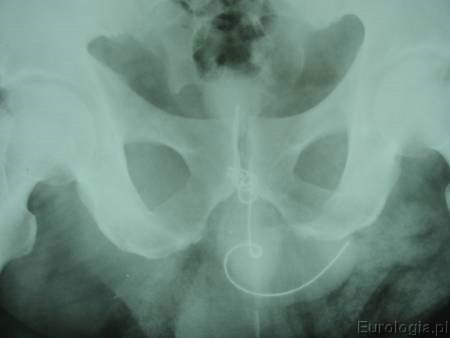

Badanie USG pęcherza moczowego nie wniosło szczegółów diagnostycznych - pusty pęcherz. Wykonano zdjęcie przeglądowe nerek i pęcherza, na którym w rzucie pęcherza moczowego widoczny jest zwój drutu z masywnymi kalcyfikacjami wprowadzony do pęcherza przez cewkę moczową.